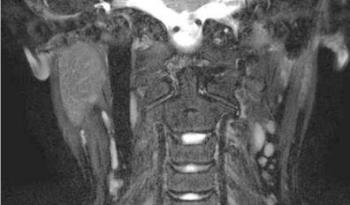

Mágneses rezonancia (Magnetic Resonance Imaging, MRI)

A számítógépes rétegvizsgálatot nem helyettesítő, hanem azt jólkiegészítő eljárás, mely elsősorban a nyálmirigyek tumoros elváltozásainak differenciáldiagnosztikájában alkalmazható módszer (12.5. ábra). Különösen jó hatásfokkal alkalmazták pleomorph adenomák recidívája esetén a kiújuló tumorok számának és kiterjedésének megítélésére (12.6. ábra). A módszer, ionizáló sugárzás alkalmazása nélkül képes nagy felbontású tomográfiás felvételek készítésére bizonyos szervekről, beleértve a nyálmirigyeket is. A módszer lényegében a különböző szövetek víztartalmáról nyújt alapvető információkat. Képes az ép és a kóros szövetek közti minimális különbség kimutatására is. A módszer hátránya időigényessége, kontraindikált volt pacemakerimplantáció, illetve intraoralis fémtárgyak (pl. rögzített fogpótlás, fix fogszabályozó készülék) esetében.

12.5. ábra. Jobb oldali ép parotis MRI-felvétele(Dr. Dobai Ágnes anyagából)

12.6. ábra. Jobb oldali parotis tumor MRI felvétele(Dr. Kollár József anyagából)